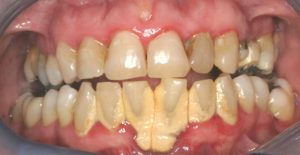

Mild to Moderate Periodontal Disease

Gingivitis is the first stage of periodontal disease. Plaque and its toxin by-products irritate the gums, making them tender, inflamed, and likely to bleed.